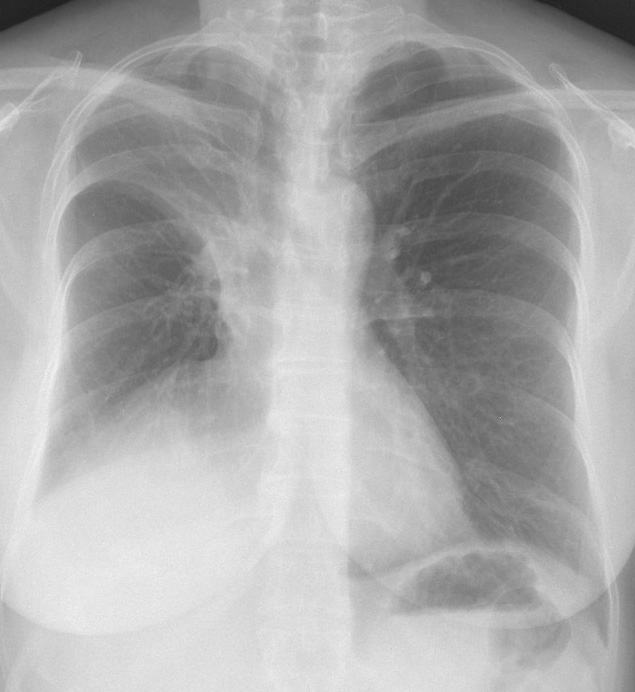

Gallery Lobar Collapse RUL Collapse RULobectomy

RULobectomy